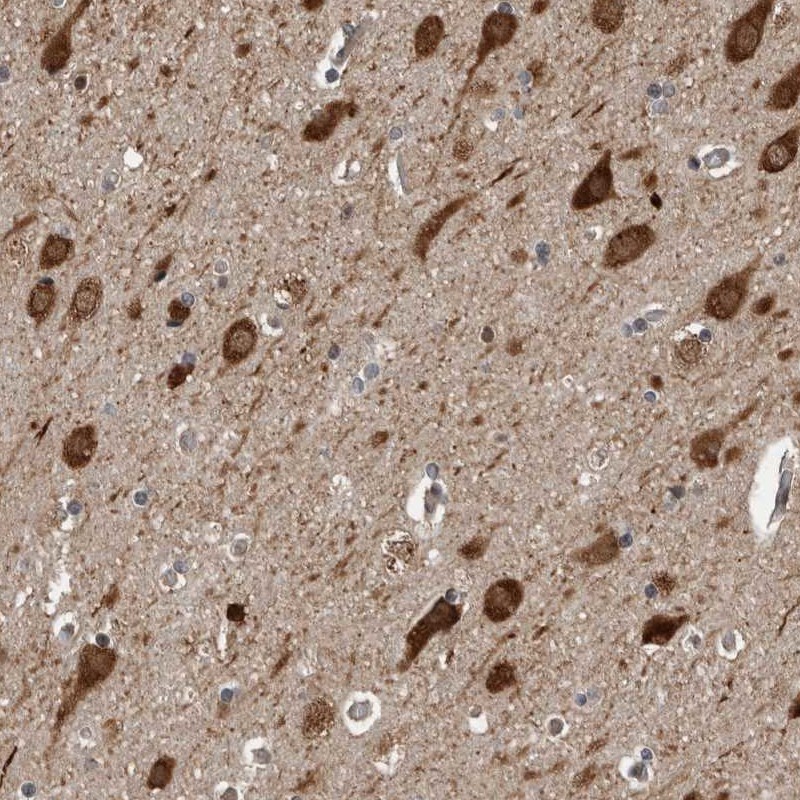

Immunohistochemical staining of human cerebral cortex shows strong cytoplasmic and nuclear positivity in neuronal cells.